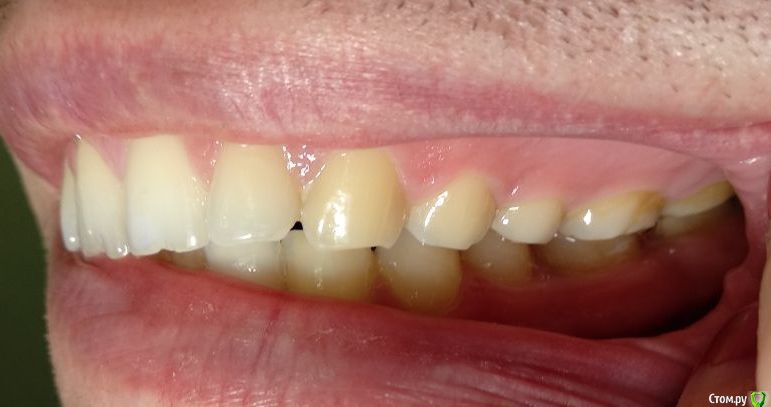

Здравствуйте! Откололся кусок зуба. 8 октября сделали КЛКТ (3Д снимок всех зубов). Вскрыли зуб, была проведена девитализация. Поставили диагноз: хронический фиброзный пульпит 37 зуба. 18 октября было проведено первичное лечение 3-х канального зуба эндомотором с использованием микроскопа и системы коффердам. Все каналы были запломбированы гуттаперчивыми штифтами на силлере методом латеральной конденсации Adseal, внутрь заложена ватка и поставлена временная пломба дентин-паста. 29 октября ортопед №1 посмотрел прицельный снимок (см. снимок зуба 2) и сам зуб, пломбу не снимал. Озвучил, что у меня низкая высота зуба, мне нужно установить культевую кобальт-хромовую вкладку и сверху покрыть металлокерамической коронкой зуб. Также сказал, что циркониевая вкладка мне не подходит из-за высоты. Однако, поскольку ортопед №1 уходил на обучение, мне было предложено обратиться в другую клинику к другому ортопеду. 1 ноября ортопед №2 посмотрев мой зуб без снимка заявил, что у меня сохранились три стенки у зуба и мне надо просто закрыть пломбой этой зуб. Поскольку ортопед №2 предложил диаметрально противоположное лечение зуба, то я решил обратиться в третью клинику. Ортопед №3 посмотрев снимок моего зуба, сам зуб, в том числе внутри (снял мою временную пломбу из дентина), заявил, что у меня низкая высота зуба и мне нельзя ставить культевую вкладку и коронку. И было предложено сделать вкладку из пресс керамики overlay. Также когда удалили временную пломбу у меня увидели кариес на этом зубе. В конце приема мне взамен снятой пломбы установили временную пломбу парасепт.

Сделал несколько фотографий, тк не совсем понял с какого ракурса делать фото с сомкнутыми зубами.